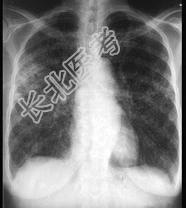

- 单项选择题女,23岁, 消瘦盗汗1月余,干咳1周, 偶痰中带血,影像如图, 最可能的诊断为 ( )

A、粟粒性肺结核

B、含铁血黄素沉着

C、弥漫性肺纤维化

D、慢性支气管炎

E、SLE肺部侵犯